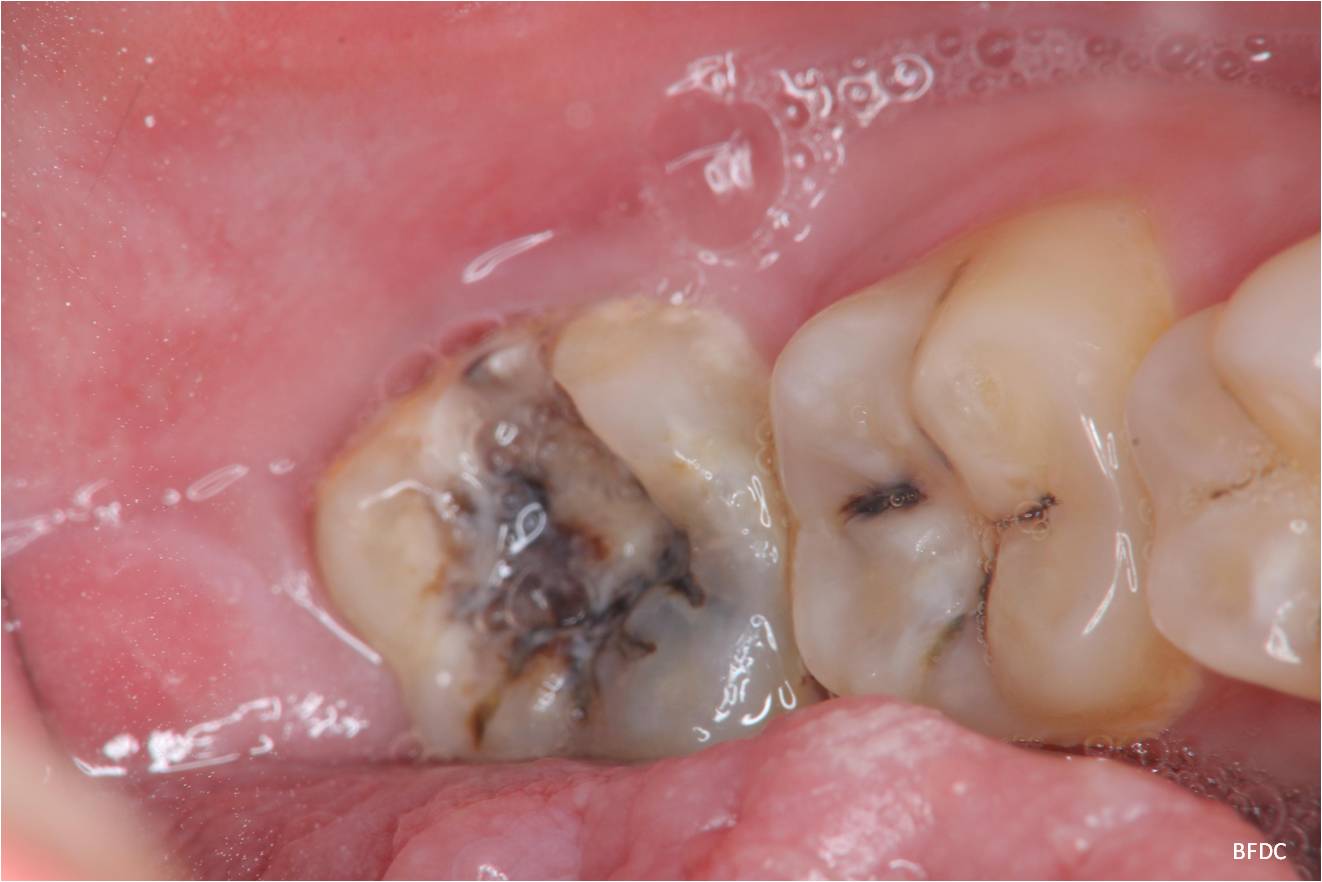

治療前,左下阻生齒深度蛀牙